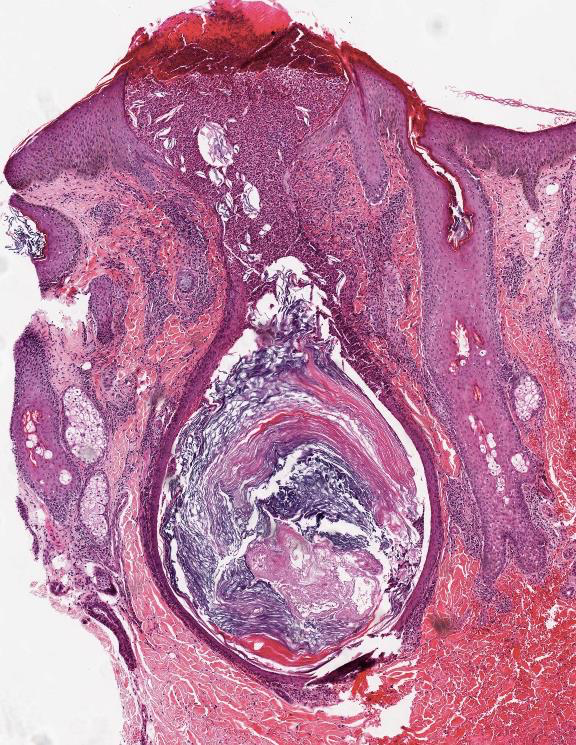

ACNE VULGARIS

• Suppurative folliculitis and Perifollicular infiltrates

• Comedo - plug of corneocytes within a widened infundibulum